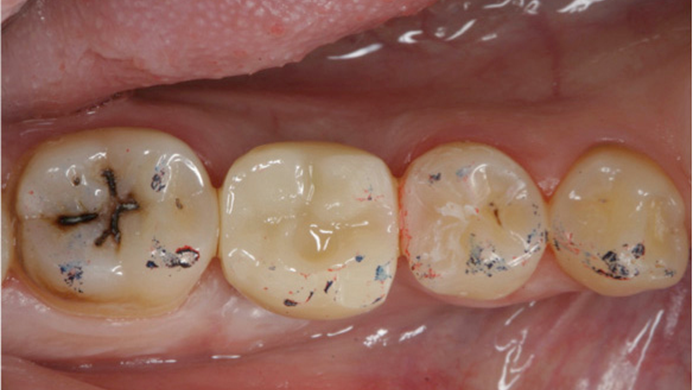

Clinical case: # 46 implant placement & GBR using i-Gen membrane for significant vertical resorption & mixed bone defect

- Courtesy of Dr. Iulian Filipov, Romania -

AnyRidge, mandibular posterior, i-Gen, resorption, bone defect, bone regeneration, space management, #46, GBR, Dr. Iulian Filipov